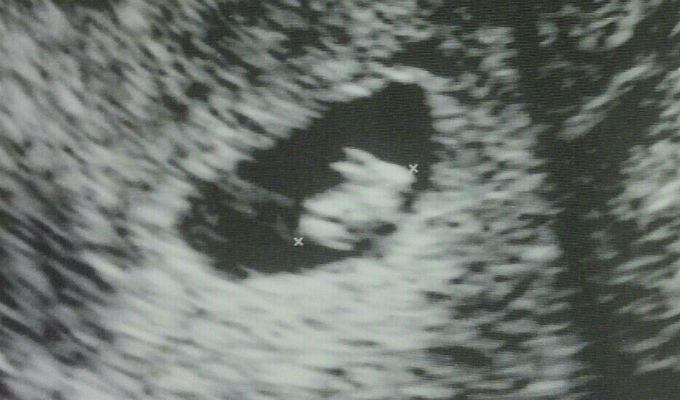

Una mujer embarazada publicó en el sitio web Imgur, una controversial foto de su primera ecografía. La imagen muestra que en su vientre vendría creciendo nada menos que un pequeño conejo.

La madre primeriza no tuvo mejor idea que colgar la imagen en la red social y le agregó la siguiente descripción: “Esta mañana fuimos a hacer la primera ecografía... Y resulta que voy a tener un conejo", bromeó la usuaria anónima.

La foto publicada el pasado viernes en el sitio web viene causando sensación, y ha sido vista por más de 800 mil cibernautas.